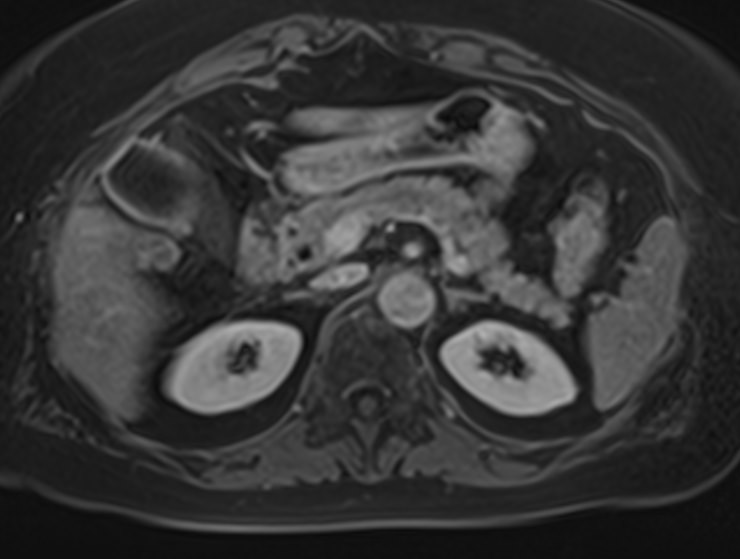

Магнитно-резонансная томография брюшной полости является наиболее информативной безопасной и эффективной методикой обследования внутренних органов. Метод позволяет проводить дифференциальную диагностику в сложных клинических случаях. Особенно это важно при противоречивых и неоднозначных данных, полученных при проведении УЗИ, рентгенографии, КТ или других обследованиях.

Методика МРТ основана на применении внешнего магнитного поля и отличается точностью и достоверностью полученных данных. Отсутствие вредного рентгеновского излучения делает процедуру безопасной и позволяет при необходимости проводить томографию несколько раз в течение короткого периода времени. Это бывает важно, например, для оценки динамики состояния патологических изменений в органах на фоне лечения.

Для расширения возможностей диагностики, при необходимости уточнения характера патологических изменений, в случае подозрения на опухолевый процесс, дополнительно применяется контрастное усиление.

Для этого в вену вводится контрастный препарат, содержащий металл гадолиний (Магневист, Гадовист, Омнискан и др). Степень и характер накопления контрастного препарата в органах и тканях позволяет различать патологические процессы. Это дает возможность, в частности, диагностировать патологические очаги минимальных размеров, что бывает особенно важно в ранней диагностике опухолей.

В клинике «Доступная медицина» МР томография проводится на новейшем высокопольном томографе экспертного класса TOSHIBA VANTAGE TITAN 1,5 Тесла. Высокая индукция магнитного поля обеспечивает повышенную четкость изображений при проведении обзорной МРТ брюшной полости, что гарантирует точность и эффективность диагностики заболеваний печени, желчного пузыря, поджелудочной железы и селезенки. Аппарат послойно сканирует исследуемую область с шагом от 1 мм в различных плоскостях, затем трансформирует результаты в трехмерные изображения превосходного качества. Для уточнения характера патологических изменений одного из органов назначается прицельная МР томография данного органа.